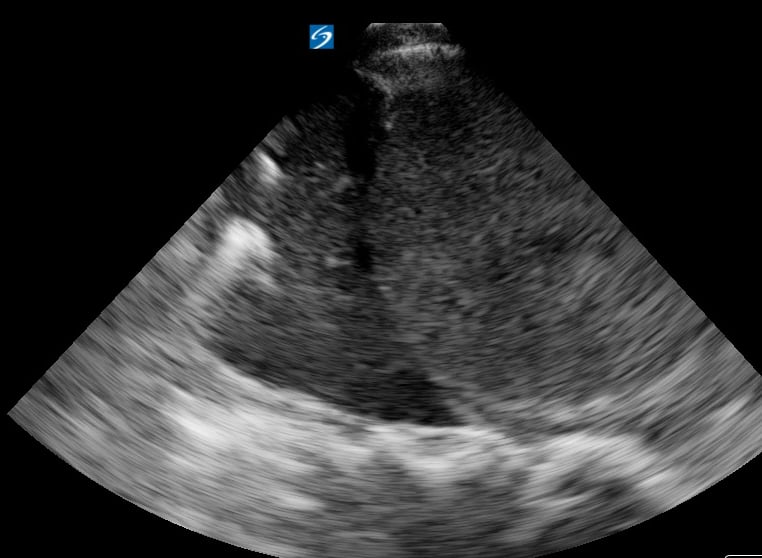

The “spine sign” in lung ultrasound refers to the abnormal visualization of the vertebral bodies above the diaphragm, a key indicator of pleural effusion. Normally, the air-filled lungs obscure the spine above the diaphragm. However, in the presence of fluid, sound waves can travel through the effusion, allowing the spine to be seen. This finding is crucial for diagnosing fluid accumulation in the thoracic cavity.

Recognizing the spine sign is essential for medical professionals using point-of-care ultrasound. Its presence confirms a significant pleural effusion, guiding further diagnostic and therapeutic interventions. This simple yet powerful ultrasound sign enhances rapid assessment in emergency and critical care settings, improving patient management.